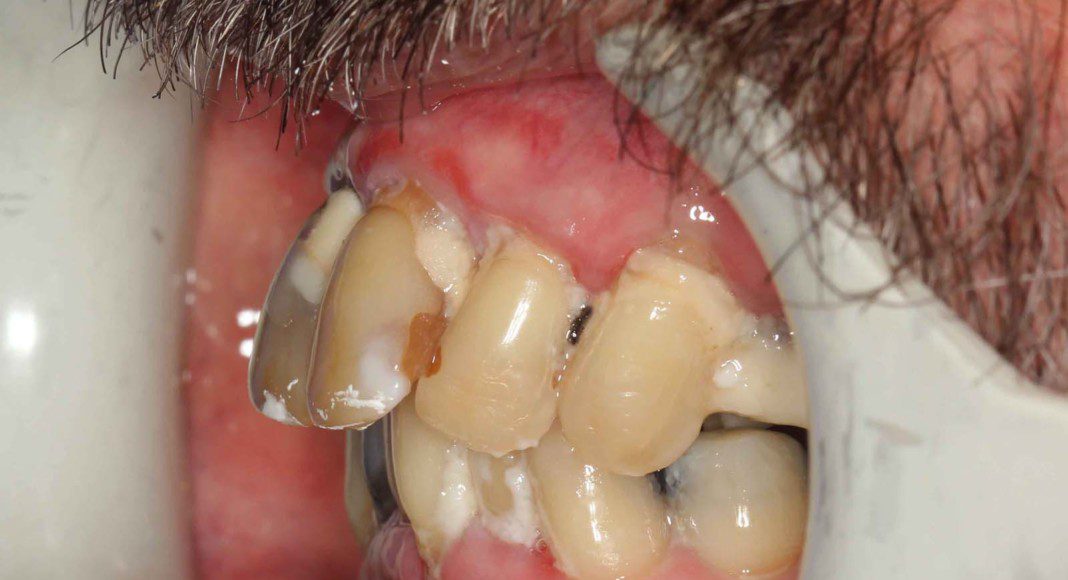

Right lateral (mirror) view of bridge. Note the “normal” contours that mimic natural teeth. Slight metal exposure of implant #4. Nothing can be “perfect” and we try to keep this from happening. However, some patients have existing bone loss that prevents perfection.